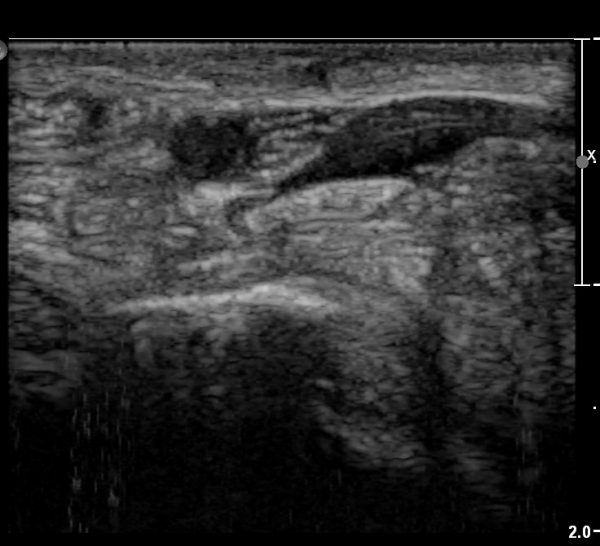

ÃÊÀ½ÆÄ ¼Ò°ß :  ¼Õ¸ñ±ÙÀ§ºÎ Ⱦ´Ü¸é°Ë»ç¿¡¼­ ¼Õ¸ñ±¼±Ù°Ç(FCR)°ú Ç¥Ãþ ¼Õ°¡¶ô ±ÁÈû±Ù(FDS) »çÀÌ¿¡

Á¤Á߽ŰæÀÌ Á¤»óÀûÀÎ ¾ç»óÀ¸·Î º¸ÀÓ(»çÁø 1).

Å½ÃËÀÚ¸¦ ¸»´ÜÀ¸·Î À̵¿ÇÏÀÚ  Á¤Áß½Å굥 ¿äÃø ÀϺΰ¡ Àú¿¡ÄÚ Á¾±«·Î °üÂûµÊ(»çÁø 2).

ÀÌ·± ¸ð½ÀÀº ¼Õ¸ñÀÇ ¿ù»ó°ñ ºÎÀ§(»çÁø 3, 4)¸¦ Áö³ª ¼ö±Ù°ü ±ÙÀ§ºÎ ±îÁö À̾îÁü(»çÁø 5).